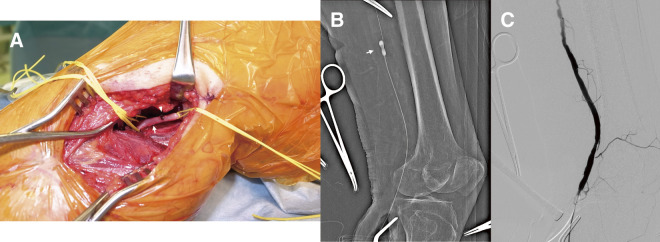

Objectives: Surgical thrombectomy has been established as an effective treatment for acute limb ischemia (ALI). Nevertheless, manipulation via the common femoral artery (CFA) to retrieve thrombus in the infra-popliteal artery sometimes proves less effective. Methods: We retrospectively reviewed patients undergoing surgical thrombectomy for infra-inguinal ALI from January 2010 to December 2022. The primary endpoint was the rate of amputation. Secondary endpoints were technical and clinical success rates, incidence of distal embolism, and freedom from reintervention. Results: A total of 35 patients underwent surgical thrombectomy where the popliteal artery or below is occluded. The CFA approach was utilized in 13, and the below-knee popliteal artery (BKPA) approach in 22. There were no differences in background between groups. The reintervention rate was lower in the BKPA group (BKPA group: 0% vs. CFA group: 30.8%; P = 0.01). The BKPA group showed a significantly lower incidence of distal embolism (BKPA group: 4.5% vs. CFA group: 38.5%; P = 0.02) and freedom from reintervention (BKPA group 100% at 12 months vs. CFA group: 68.7% at 12 months; log-rank P = 0.01). Conclusions: The BKPA approach-first strategy for surgical thrombectomy in the management of ALI is feasible with better outcomes compared with the CFA approach.